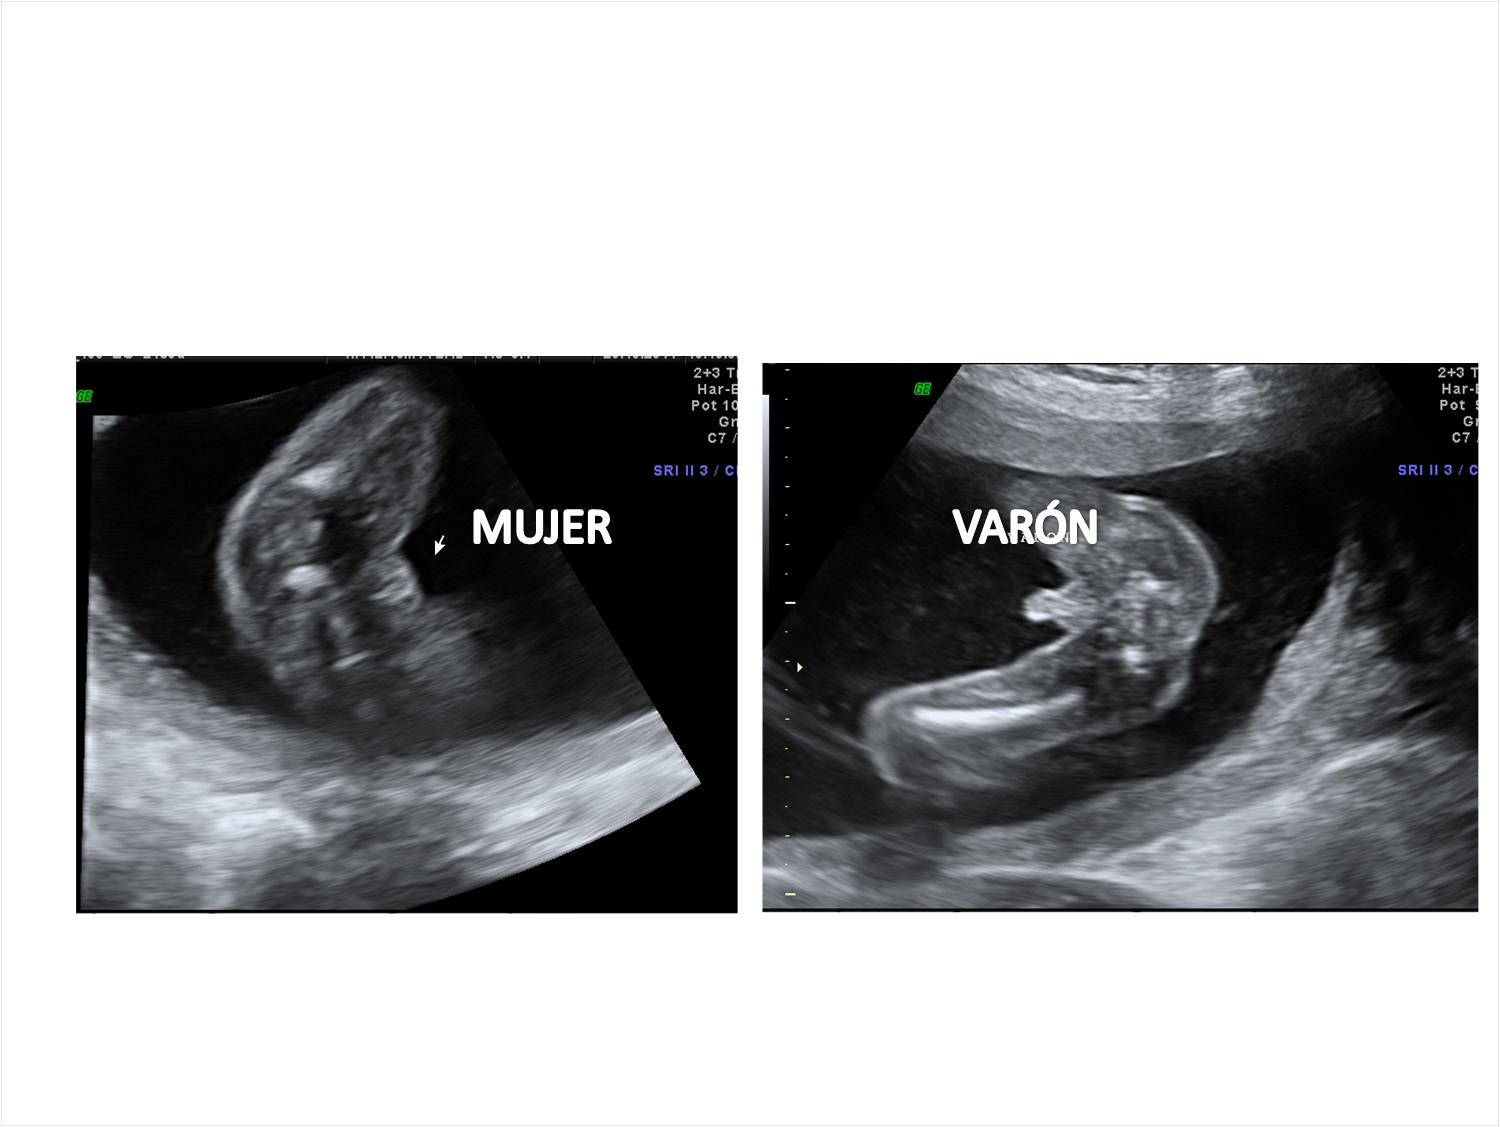

Aplicaciones en obstetricia y ginecología:.

que es una ultrasonografia La ultrasonografía eus ofrece una imagen. La denominación ecografía o ultrasonido se refiere a un procedimiento que emplea ondas sonoras de alta frecuencia para ver el interior del cuerpo, colocando un transductor o. Una ecografía, también conocida como sonograma, es una prueba de diagnóstico por imagen que utiliza ondas sonoras (ultrasonido) para crear imágenes de órganos,. La ultrasonografía es un método de diagnóstico por imagen que utiliza un transductor para emitir. Un ultrasonido de la mama es una técnica de imágenes que se utiliza comúnmente para detectar tumores y otras anomalías en los senos. Aplicaciones en obstetricia y ginecología:. El ultrasonido es un examen médico no invasivo que ayuda a los médicos a diagnosticar y tratar condiciones médicas. Descubre qué es un ultrasonido o ecografía y cuáles son sus usos en el cuidado de la salud.

Prácticas para un Examen de Ultrasonografía